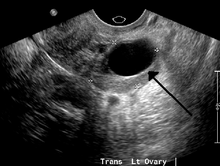

| A simple ovarian cyst of most likely follicular origin | |